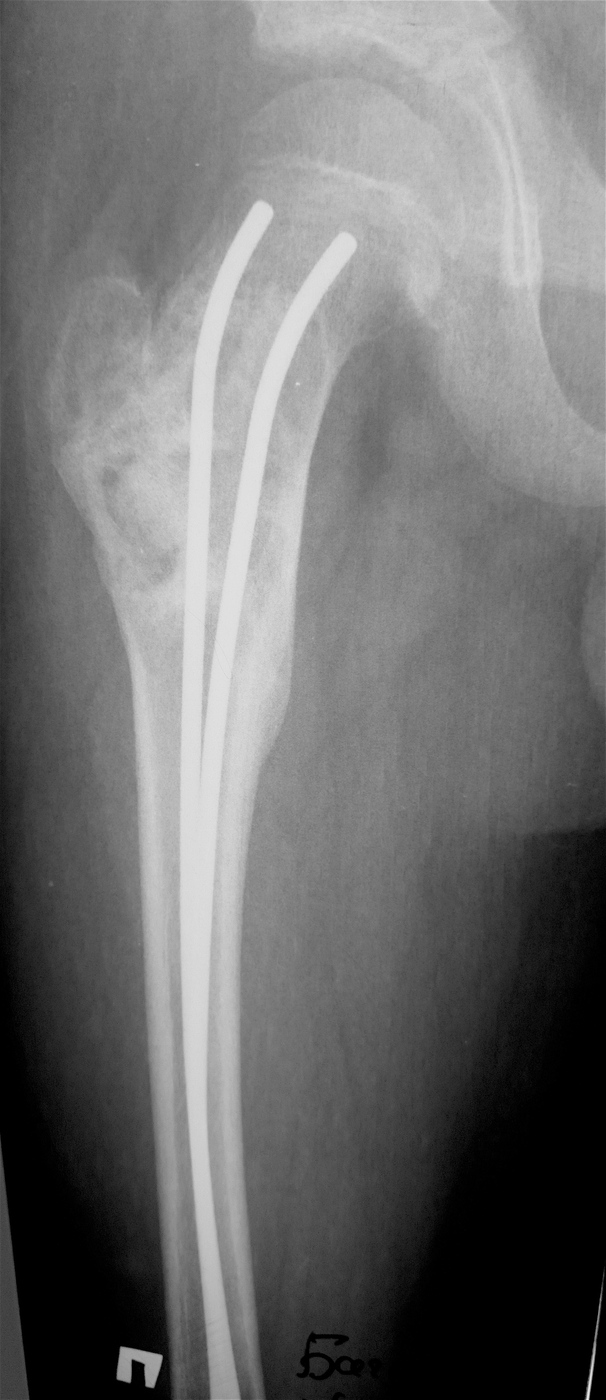

Выполнена резекция с аллопластикой губчатыми и кортикальными биоимплантатами "Лиопласт".